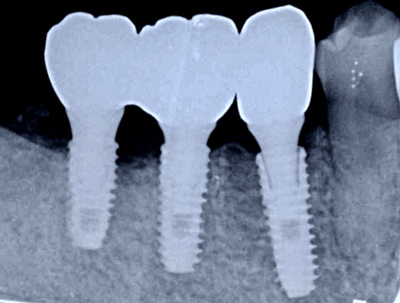

奈良 生駒 石切 インプラント 寝ながら無痛インプラント 良心価格 10年保証 再生医療 まず、CT画像で現状を伝え、充分な治療計画を元にカウンセリングした結果、インプラント施術を行うことになりました。緊急手術のため今回は、技工士さんに依頼した手作りサージカルガイド(手術用のナビゲーション:無料)を使用しました。

奈良 生駒 石切 インプラント 寝ながら無痛インプラント 良心価格 10年保証 再生医療 3本のインプラント移植抜歯穴に人工骨とCGFを混ぜ合わせて埋めた「骨の再生治療(無料)」も同時に行いました。

奈良 生駒 石切 インプラント 寝ながら無痛インプラント 良心価格 10年保証 再生医療 奈良 生駒 石切 インプラント 寝ながら無痛インプラント 良心価格 10年保証 再生医療 常時ー静脈麻酔鎮静 再生医療 良心的価格 石切 生駒 奈良 インプラント特化 使用インプラント:USAオステム社製 TⅡ-SA 左端から長さ8.5,10,11.5㎜の順。太さはいずれも直径4㎜。